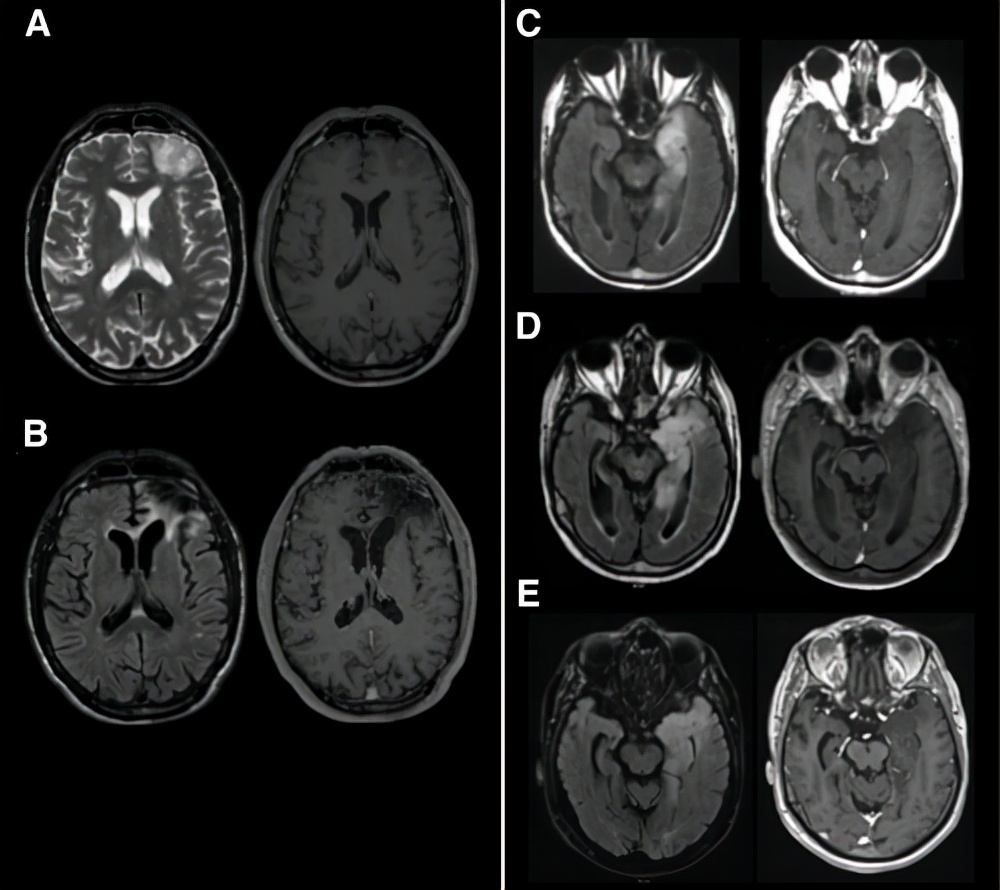

图示: 2 级胶质瘤老年患者的治疗案例。 (A):一名 70 岁男性癫痫患者的术前磁共振成像 (MRI)。该患者接受了手术切除,明确诊断为 1p/19q共缺失、IDH1 突变,2 级少突胶质细胞瘤。没有进行其他辅助治疗。 (B):在手术后 5 年的最后一次随访中,患者状况良好(Karnofsky 表现评分 [KPS] = 90%),MRI 复查病灶稳定。 (C):诊断性 MRI 显示一名 73 岁患者的左侧颞部浸润性病变。进行了活检,无1p/19q共缺失、IDH1突变的 2 级星形细胞瘤的诊断。对患者进行了密切随访,没有进一步治疗。 (D):五年后,观察到进展的影像迹象,并开始用替莫唑胺治疗。 (E):最后一次随访,化疗后 4 年,患者(现 82 岁)临床状况(KPS = 80%)和影像上病变稳定。